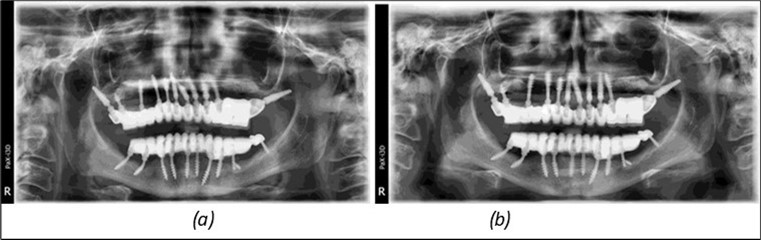

June 2022: Patient presented to our clinic for immediate-loading implant treatment At the time of presentation in 06. 2022, radiologically, advanced peri- implantitis is observed around the implants, with loss of native bone in the affected distal areas (Figure 1)

Figure 1.Panoramic overview picture before rehabilitation 06.2022

Figure 3.Panoramic pictures after removal of implants affected by peri-implantitis, extractions, alveolar crest regularization, and insertion of corticobasal and TPG implants (07.2022)

Figure 14.Rx panoramic final situation control: (a) Panoramic X-ray with the addition of a distal BCS implant in quadrant 3 at 11.2022; (b) Control X-ray, 10.2023.

The results of rehabilitation treatment with corticobasal and compressive implants with a polished surface after the failure of two stage implants were highlighted over a period of 3 years and 3 months as being very good (Figure 14, Figure 15), with the patient completing a satisfaction survey in this regard. Certainly, it is necessary to continuemonitoring these results in the long term.